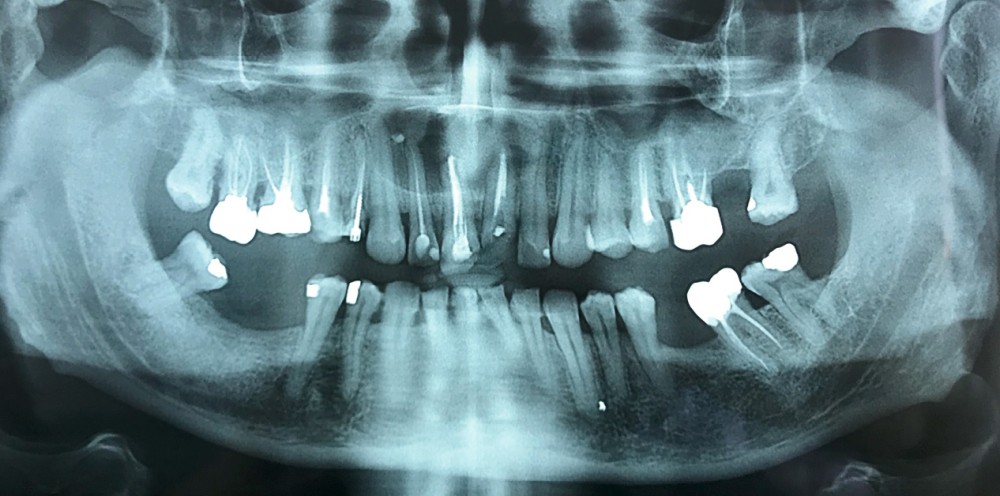

- Plus rarement, extension latérale jusqu’aux prémolaires de façon asymétrique (fig. 5).